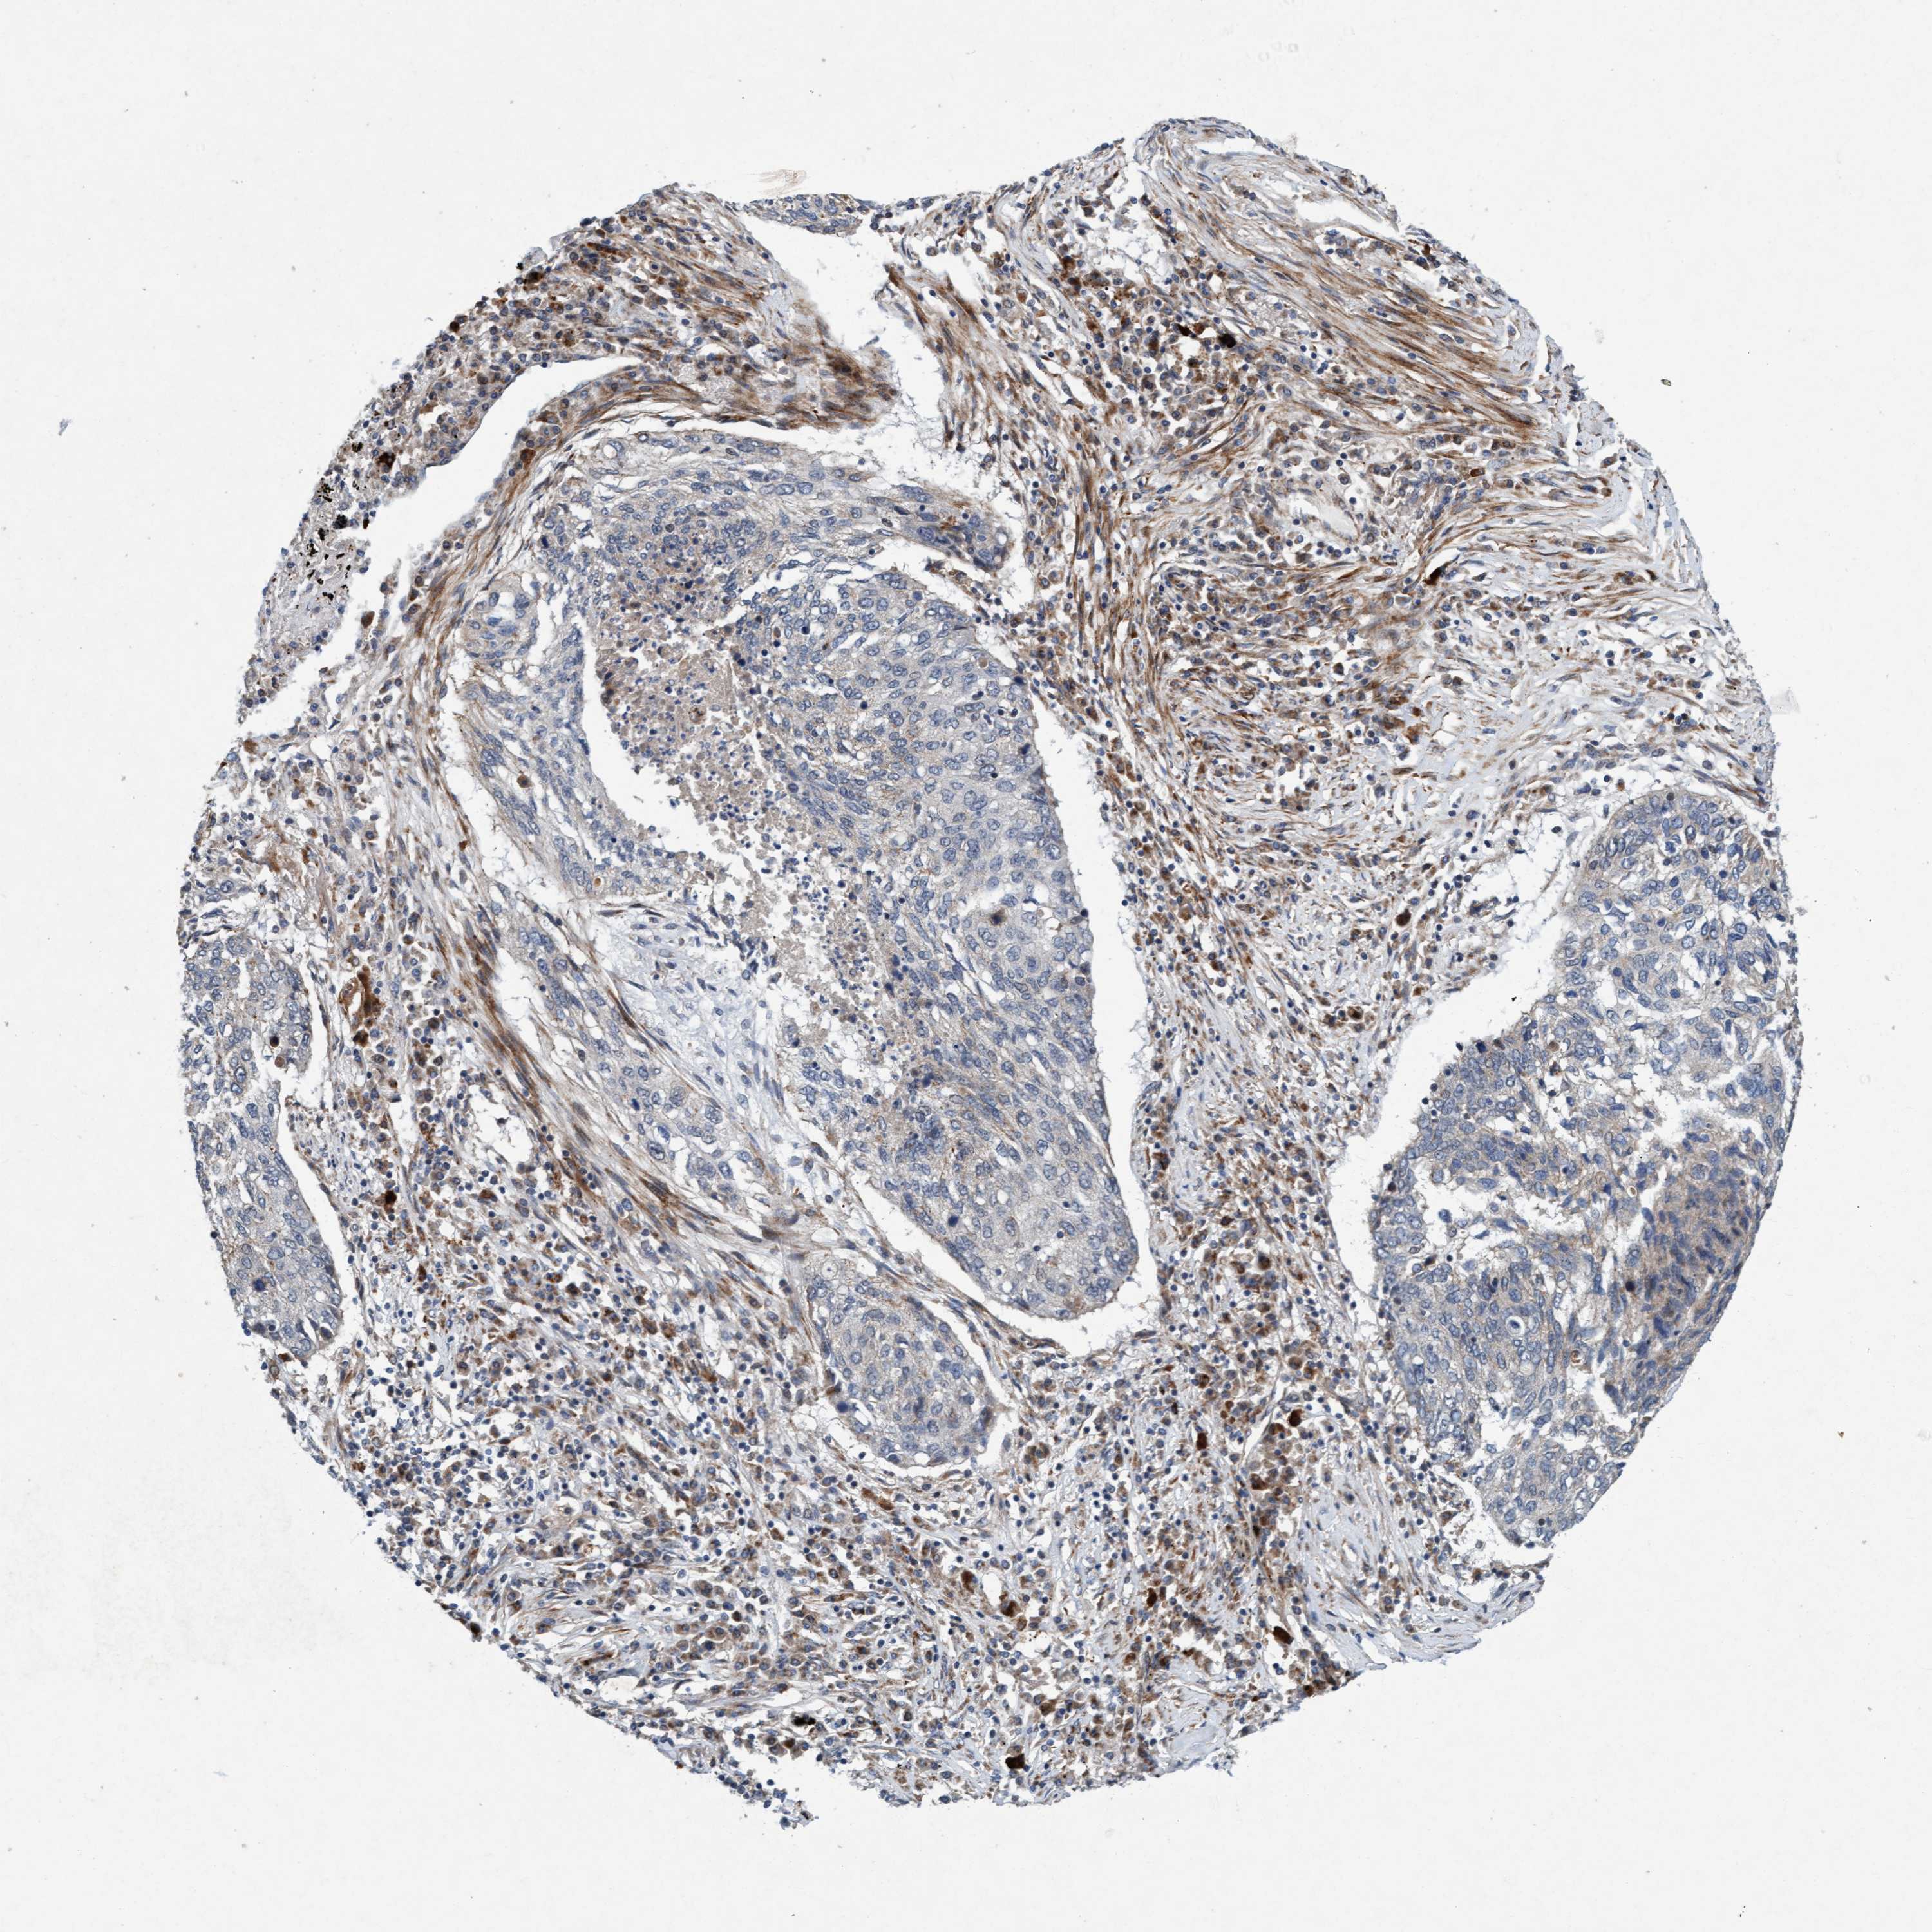

CANCER LUNG CANCER Show tissue menu

LUAD TCGA LUAD VALIDATION LUSC TCGA LUSC VALIDATION PROTEIN LUAD CPTAC PROTEIN LUSC CPTAC PROTEIN EXPRESSION